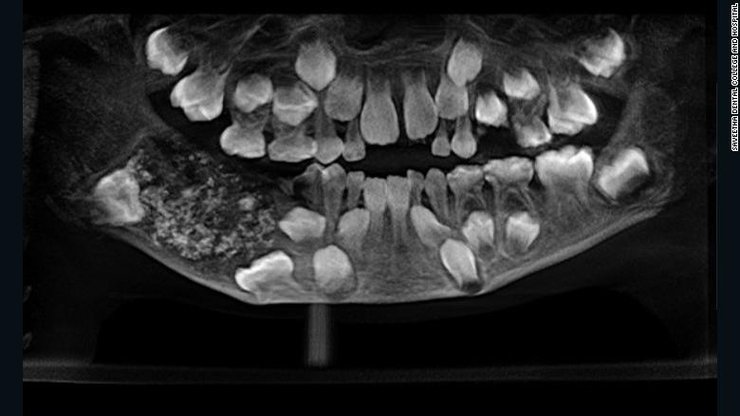

Рентген челюсти 7-летнего ребенка. Фото: Saveetha Dental College and Hospital

Мальчик был госпитализирован в южном городе Ченнаи из-за отека и болей в нижней челюсти. На рентгене врачи увидели в нижней челюсти мальчика мешок, заполненный недоразвитыми зубами.

"Всего было 526 зубов, размер которых варьировался в диапазоне от 0,1 мм до 15 мм. Даже у самых маленьких зубов имелся корень и эмаль", – заявила доктор Пратиба Рамани, руководившая операцией.